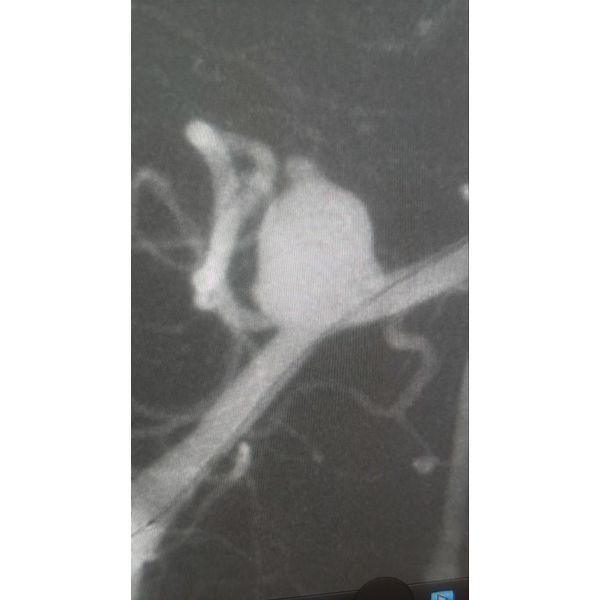

Пациентке провели малоинвазивное рентгенэндоваскулярное вмешательство — эмболизацию аневризмы позвоночной артерии. В ходе операции через тонкий катетер в просвет аневризмы ей последовательно под рентгенологическим контролем ввели микроспирали, что позволило устранить патологический ток крови в области аневризмы и минимизировать риск повторного кровотечения.